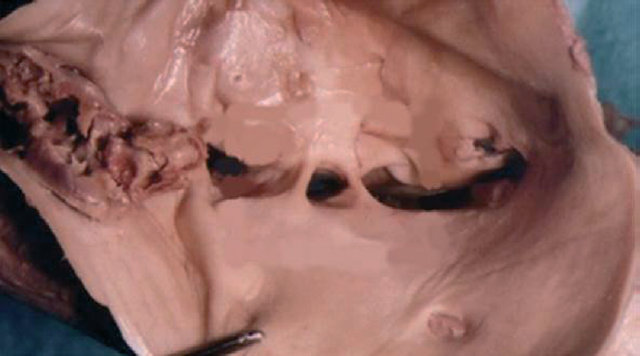

H. Mitsuoka et al. (2014) при аутопсии 28 трупов выявили спайки в просвете вен в 6 (21,4 %) случаях (у 3 мужчин и у 3 женщин). Распространенность спаек составляла 15,8 % в группе A (полное или частичное сдавление правой общей подвздошной артерией левой общей подвздошной вены) и 33,3 % в группе B (правая общая подвздошная артерия сдавливает нижнюю полую вену) (рис. 10, 11) [44].

Рис. 10. Шварты (синехии, спайки) в просвете левой общей подвздошной вены [44]

Рис. 11. Распространенность спаек в просвете вен по H. Mitsuoka et al. (2014) [44]. Группа A — полное или частичное сдавление правой общей подвздошной артерией левой общей подвздошной вены (бифуркация аорты на нижнем уровне); группа B — правая общая подвздошная артерия сдавливает нижнюю полую вену (бифуркация аорты на высоком уровне)